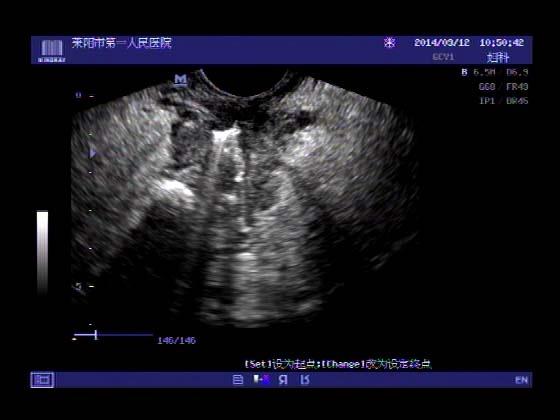

超声入门贴353-----直肠癌伴肝转移

女,66岁